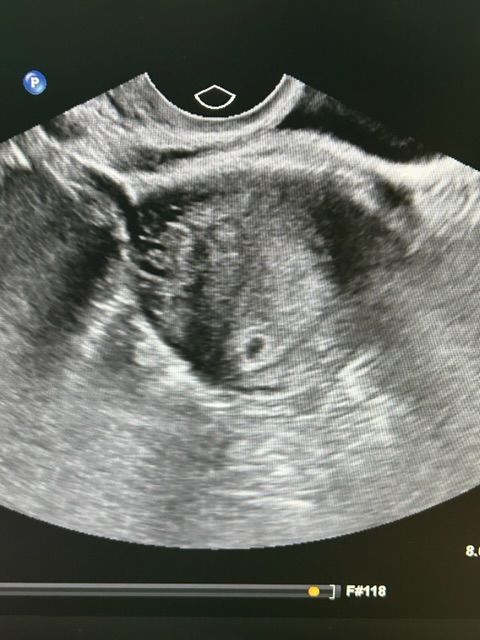

Нашли) 5мм ❤️